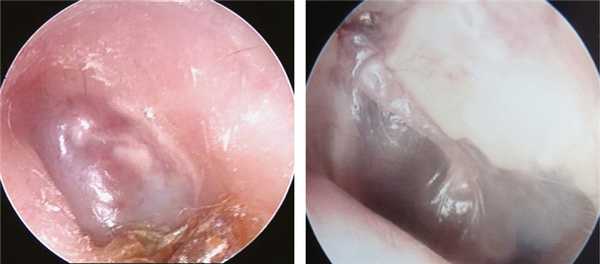

У всех пациентов после первого реконструктивного этапа при отомикроскопии тимпанальная мембрана была тонкой, с наличием в толще барабанной перепонки ТСК комплексов или аутохрящевой полупластины в центре или в задних ее квадрантах (рис. 1).

Рис. 1. Эндофотография барабанных перепонок у больных тимпаносклерозом перед стапедопластикой.